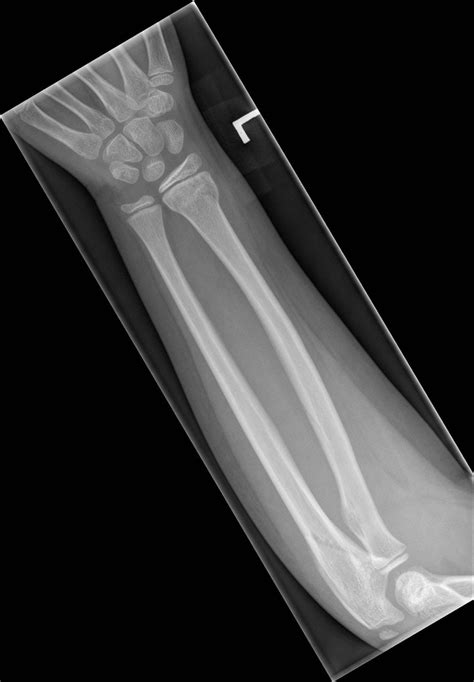

• X-Rays: X-rays are the primary imaging tool used to confirm the presence and severity of a fracture. They provide detailed images of the bones and can show the exact location and type of fracture.